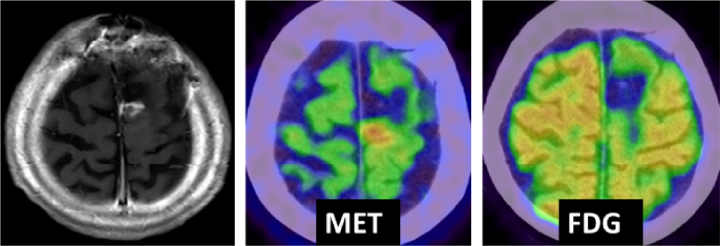

PET検査(ポジトロン断層撮影法)は癌領域では欠かせない検査になっていますが、 脳腫瘍の診断においてはメチオニンという核種を使用した検査が有用と言われています。 最近、メチオニンPETの有用性を証明し、かつ薬事承認を得ることを目的とした臨床研究が終了し、 有効性を証明することができました。現在、この試験結果をもとに、 メチオニンPETが脳腫瘍診断で日常診療として使用できるように準備を整えております。 また、新規の核種を用いた診断方法も今後登場することが分かっており、 これらの診断方法を用いた脳腫瘍診断の前向き研究、 診断結果と予後や治療成績との比較などの後方視的観察研究を行っています。